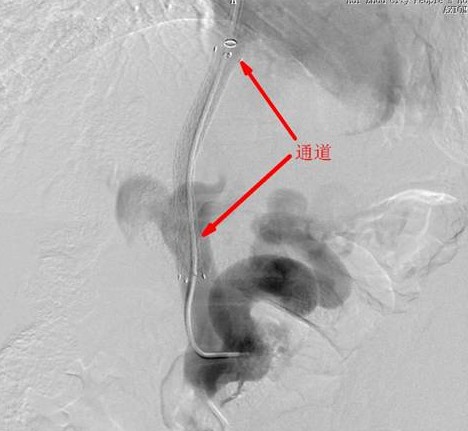

1031下午,患者被推进DSA手术室,在陈教授的指导下,凌主任及徐永辉医生为患者进行局部麻醉,右侧颈部静脉穿刺成功后插入10F金属血管鞘并导入8F导引导管进入肝静脉造影,肝静脉扩张增粗,经导引导管内导入TIPSS穿刺套装,调整角度后对准门静脉左支进行肝内穿刺并回抽见静脉血,再用高压注射器造影证实肝静脉——门静脉穿刺成功(这一步是这手术的技术难点,也是关键,其决定着手术是否顺利,以及成败)。再导入导丝进入门静脉,导丝导引5F-椎动脉管进入门静脉内,造影显示门静脉主干明显增粗:测量门静脉压力为45cm水柱(正常范围为1324cm)。再将导管进入脾静脉处高压造影,显示脾、食管及胃底静脉严重增粗迂曲。撤出导管并导入球囊,送至肝静脉与门静脉间的穿刺通道,高压扩张,撤出球囊:在通过指引导管植入FVM8*8带膜支架,在DSA透视下精确定位后释放支架安放位置至关重要),门体静脉分流通道成功建立;重复导入5F导管高压注射器造影证实分流通道通畅,并测定门静脉压力为28cm水柱,压力明显下降。胃左静脉造影显示胃左静脉及胃底食管静脉明显呈腊肠样重度扩张,最大直径的钢圈无法栓塞,经导管注射10ML甘油酸钠泡沫硬化剂,再次造影证实胃左静脉血流明显减慢。撤管把鞘按压包扎穿刺部位后,历经两个多小时的手术顺利完成,患者安全返回病房。

TIPSS术简单的说就是在肝静脉及门静脉之间建立一个人工分流通道,相当于在肝内人工开凿了一道导流泄洪渠,使淤滞高压的门静脉的血液得到有效的分流,降低门静脉压力,防止再次发生消化道大出血。由于其手术难度大、风险高、技术精度强,是公认代表外周介入治疗最高水平的标志性手术,目前国内能开展此手术的医院不是很多,此手术成功完成标志着我院外周介入达到了较高的水平